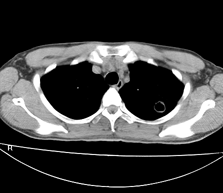

左肺上叶尖后段胸膜下可见两个类圆形薄壁空洞,内外壁较光滑,腔内为气体密度,支持结核性薄壁空洞。

左肺上叶后段见两个孤立圆形厚壁空洞,无液平及壁结节。周围清晰,无卫星灶。结合病史,如此大的病灶病人毫无感觉,另外周围如此清晰,应能排除结核空洞;肺囊肿壁应更薄,如合并感染可增厚,但周围应模糊。本人考虑:肺韦格肉芽肿。

左肺上叶后段见两个孤立圆形厚壁空洞,无液平及壁结节。周围清晰,无卫星灶。结合病史,如此的病灶病人毫无感觉.考虑1肺部感染[注意新隐球菌感染----中华放射学杂志---2006----第一期-----104页]。2肺囊肿。请指教!!!

左上叶尖后段可见两个中等壁厚空洞,腔内无液平,内外壁光整,局部轻度胸膜增厚,首虑结核。

考虑肺囊肿可能性大。不支持结核是因为周围肺野内未见明显卫星灶及纤维索条,不支持韦格氏肉芽肿是因为内壁及外壁均很光整,壁厚薄一致,而韦格氏肉芽肿洞壁厚薄多不均匀,内壁多不规则,其内可有形态不规则的内容物。

左肺尖后段的两个薄壁(纵隔窗)含气囊样病变,壁厚薄较均匀、光整、内无液气平形成、其邻近肺野见

少许渗出、未见卫星灶,其余肺野未见明显支气管播散灶(楼主虽然未上传全其他层面图片,但认为因正常而未上传)。

综合上述:考虑为肺囊肿合并感染,不支持结核空洞(虽然病变位于结核好发区,但认为这么明显的结核空洞应该有明显的肺内支气管播散灶)。